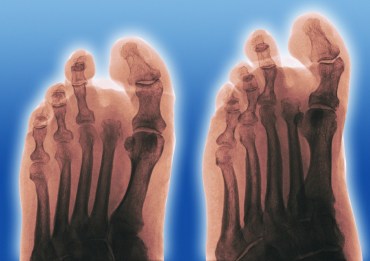

“It’s the leading cause of blindness in working-aged adults in Australia; it’s a leading cause of kidney failure leading to dialysis.